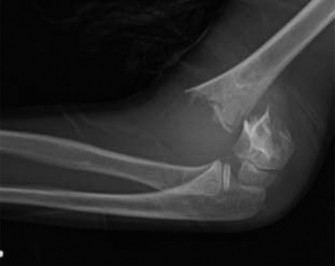

Plain Radiography Analysis

Standard orthogonal imaging, consisting of true anteroposterior and true lateral radiographs of the left elbow, was obtained in the emergency department. Accurate radiographic interpretation is heavily reliant on understanding the pediatric ossification centers, commonly remembered by the mnemonic CRITOE (Capitellum, Radial head, Internal/Medial epicondyle, Trochlea, Olecranon, External/Lateral epicondyle), which appear sequentially at approximately 1, 3, 5, 7, 9, and 11 years of age.

- Anteroposterior View: The AP radiograph revealed a complete, transverse fracture line propagating through the supracondylar region of the distal humeral metaphysis, proximal to the olecranon fossa. The distal fracture fragment demonstrated significant posterior and medial displacement relative to the humeral shaft. The medial displacement is a critical observation, as it dictates the required reduction maneuver (pronation) to tension the intact medial periosteal hinge.

- Baumann's Angle: This angle is formed by the intersection of a line drawn down the longitudinal axis of the humeral shaft and a line drawn along the physeal line of the lateral condyle. The normal range is typically 64 to 81 degrees, though comparison to the contralateral uninjured side is the gold standard (a difference of >5 degrees is considered abnormal). In this patient, Baumann's angle was measured at 55 degrees. This significant decrease indicates a severe varus collapse of the distal fragment. Failure to correct this angular deformity will result in a clinical cubitus varus (gunstock) deformity, which, while primarily cosmetic, can lead to late-onset posterolateral rotatory instability or tardy ulnar nerve palsy.

- Lateral View: The lateral radiograph is paramount for assessing sagittal plane displacement and angulation. It confirmed a complete fracture with severe posterior displacement of the distal fragment.

- Anterior Humeral Line: A line drawn down the anterior cortex of the humeral shaft should normally intersect the middle third of the capitellar ossification center. In this radiograph, the anterior humeral line passed entirely anterior to the capitellum, confirming posterior displacement and extension angulation of the distal fragment.

- Radiocapitellar Line: A line drawn through the longitudinal axis of the radius must bisect the capitellum in all radiographic views. This line remained intact, ruling out a concomitant radial head or neck dislocation (Monteggia variant).

- Teardrop Sign: The normal teardrop shape, formed by the anterior aspect of the coronoid fossa and the posterior aspect of the radial fossa, was completely disrupted, further confirming the fracture through the supracondylar region.

- Fat Pad Sign: While the fracture was grossly obvious, the presence of a large posterior fat pad sign (lifting of the joint capsule by hemarthrosis) and an elevated anterior "sail sign" were noted, indicative of a significant intra-articular effusion.